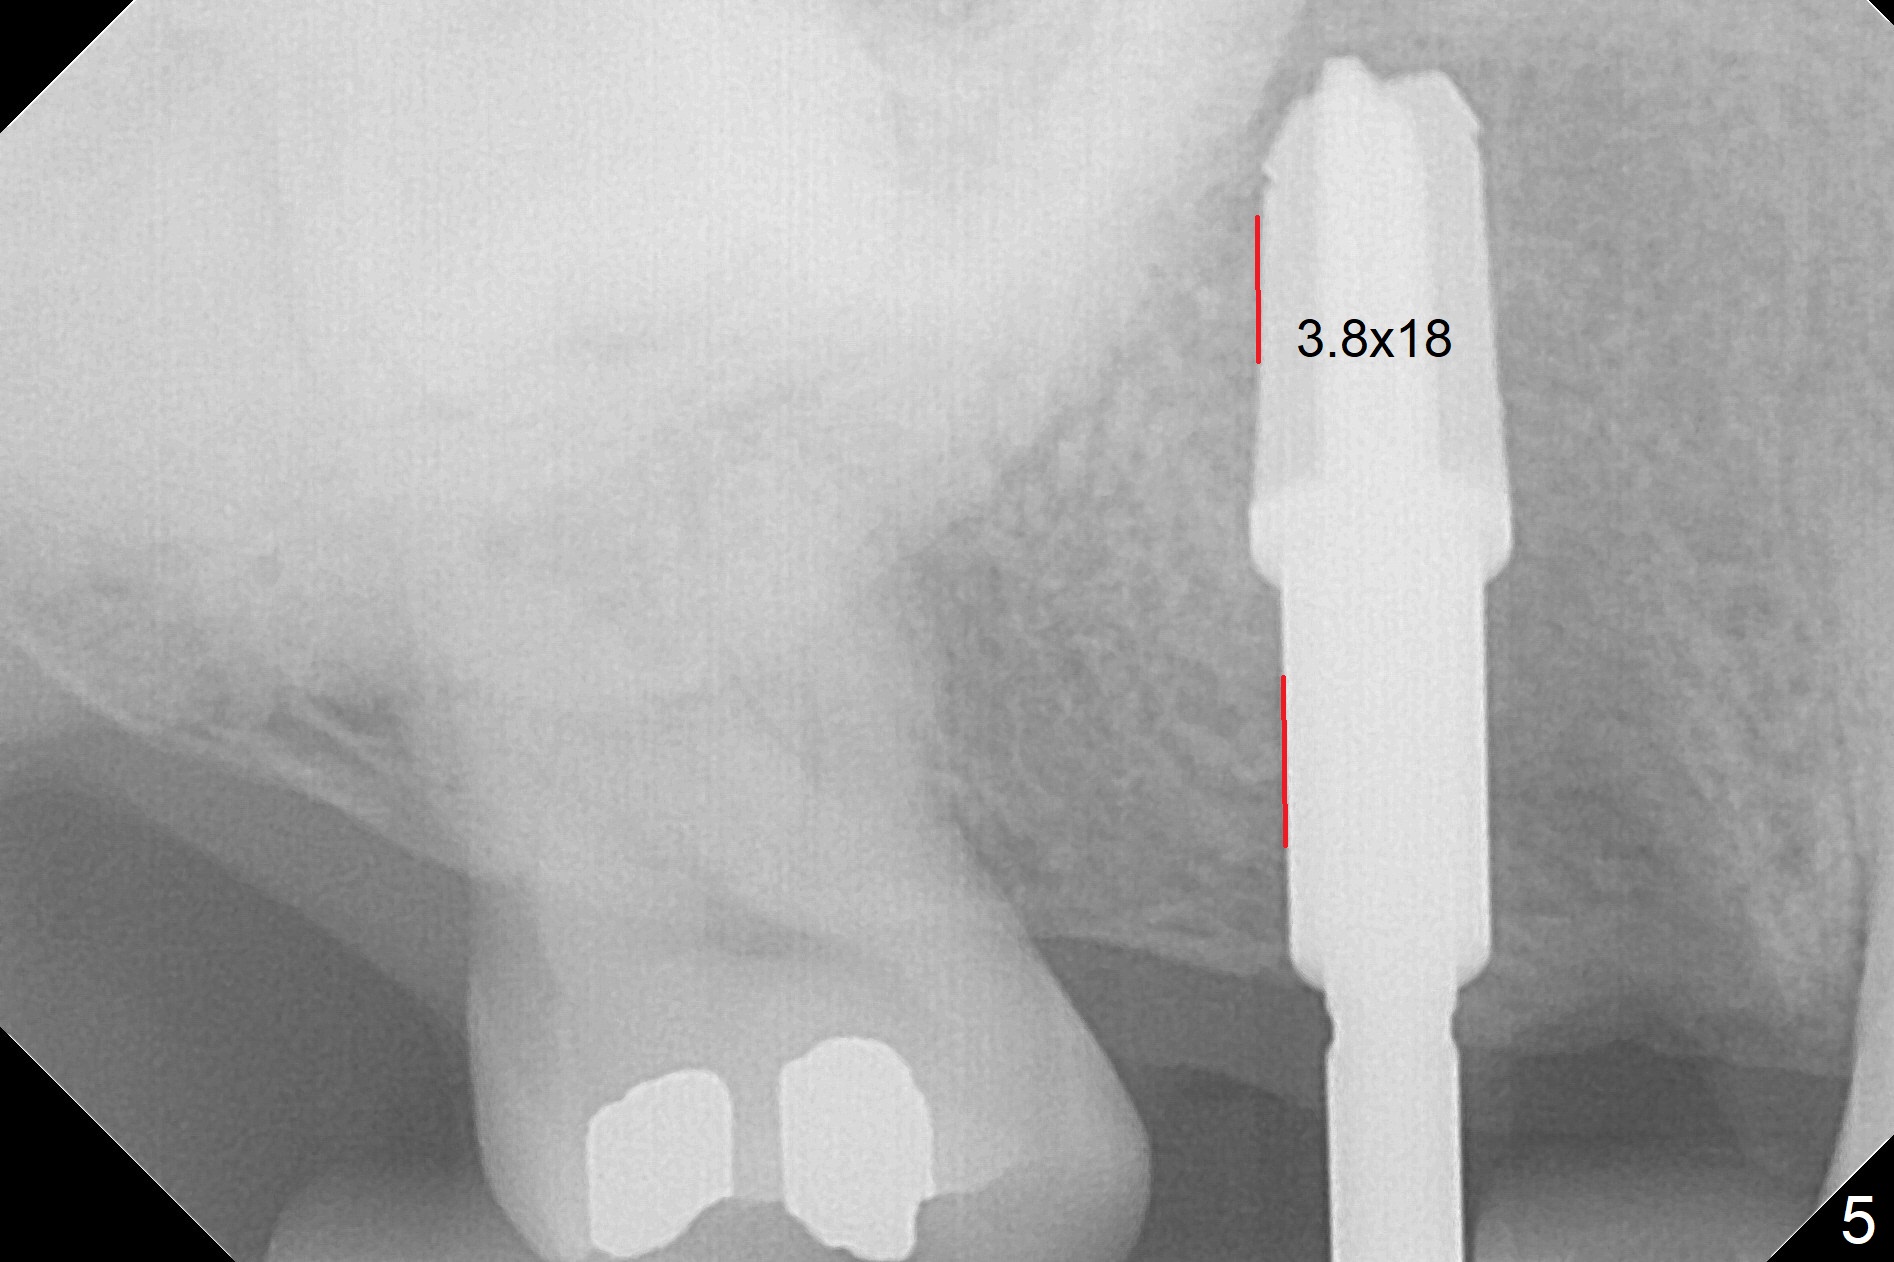

The palatal cusp of the affected 2nd premolar is apparently rotated distal (Fig.1). It is more obvious for the socket (Fig.2): the palatal (P) portion of the socket is more distal than the buccal (B) one. When the gauze is removed (Fig.3), Lindamann bur is used to remove the disto(D)palatal bone of the socket (data not shown), followed by starter drill in the DP wall obliquely (Fig.3'). Once the drill enters the bone for 1-2 mm, the bur is straightened and pushed slightly distal (Fig.3''). Fig.4 shows a parallel pin distal (overcorrect) to the original socket (Fig.4 red dashed line). Sequential osteotomy is conducted until 3.8x13 mm drill for 18 mm (Fig.5): note the 2 steps of the osteotomy (red lines). Since the apical portion of the osteotomy is larger than the drill, a larger implant than expected (5x16 mm) is placed. The implant ends up in the middle of the edentulous area (due to the stepped osteotomy; Fig.6-9; >60 Ncm). Vera allograft is placed (Fig.7-9 *) prior to and after placement of a 6.5x4(3) mm abutment (Fig.8-10). The remaining socket opening is sealed with a piece of Collagen plug (Fig.10 *). The socket is then closed by an immediate provisional (Fig.11 P). The abutment is retightened 2 months postop (Fig.12,13). The crown is cemented 4.5 months postop. Panoramic X-ray and CT are taken nearly 7 months post cementation (Fig.14,15) when the patient is ready for #30 implant guide preparation.